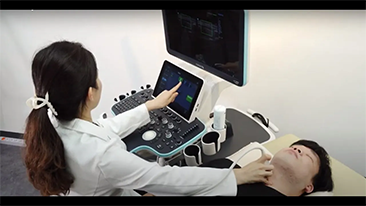

Mindray, ?irketin kuruldu?u gĂŒnden bu yana sĂŒrekli olarak tan?sal do?rulu?u iyile?tirmeye ?al??maktad?r. Devrim niteli?indeki ZONE Sonography? Teknolojisi ile desteklenen Resona 7ânin yeni ZST+ platformu, b?lge g?rĂŒntĂŒsĂŒ alma ve kanal veri i?leme ?zellikleri ile ultrason g?rĂŒntĂŒsĂŒ kalitesini daha ĂŒst bir dĂŒzeye ??kar?yor.

Resona 7, ĂŒstĂŒn dĂŒzeyde g?rĂŒntĂŒ kalitesine ek olarak, vaskĂŒler hemodinamik de?erlendirmesi i?in devrim niteli?indeki V Ak??? ile fetĂŒs CNS tan?lamas? i?in 3 boyutlu veri kĂŒmesinden dĂŒzlem g?rĂŒntĂŒsĂŒ alma konusunda en iyi birime sahip oldu?undan, klinik ara?t?rma yeterliklerini de art?rmaktad?r. En sezgisel, harekete dayal? ?oklu dokunmatik i?letim ile tĂŒm temel klinik ?zellikleri bir araya getiren Resona 7, ultrason yenili?i konusunda ger?ek anlamda yeni dalgalara ?ncĂŒlĂŒk ediyor.